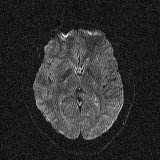

Figure 3: Example axial slice from the STE brain dMRI, involving b-values of 0, 1000 and 4000 s/mm2.

2.6 Brain dMRI by spherical b-tensor encoding

We reused the dataset described in [24]. Images were acquired using the MAGNETOM Prisma 3T (Siemens Healthineers, Germany) system. A research pulse sequence was used [25]. One volunteer was enrolled. However, as the original paper was targeted at dMRI super-resolution reconstruction, eight volumes were acquired with differently rotated fields of view. Namely, the FOV was rotated about the anteroposterior axis, starting in the axial orientation, and then at angles of 22.5, 45, 67.5, 90 (sagittal), 112.5, 135, 157.5 degrees. b-values of 0, 1000 and 4000 s/mm2 were used with 2, 4 and 15 repetitions, respectively, for each field of view. The images have 1.58×\times×1.58×\times×7.2 mm3 voxels and matrix size of 132×\times×132×\times×26. An example slice is shown in Figure 3.